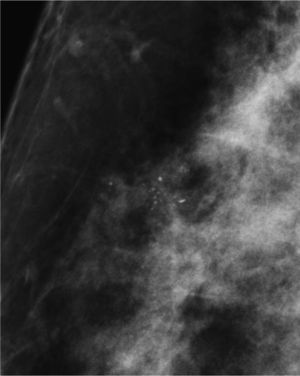

Las calcificaciones indeterminadas, como las demás, pueden ocupar una zona extensa de la mama (fig. 8), ser segmentarias (cuando ocupan un segmento) o estar agrupadas (fig. 9)6.

Como su nombre indica, son calcificaciones que hacen sospechar un proceso neoformativo subyacente.

Pueden aparecer de forma aislada o asociadas a una masa palpable o a una distorsión del parénquima mamario.